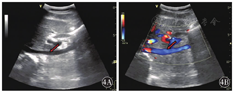

患者1女性,35岁。因"反复双下肢浮肿3个月"于2018年10月19日入院。入院后于2018年10月23日行彩色多普勒超声检查提示下腔静脉近段血流充盈缺损,管腔内为不规则、实质性、混合回声填充并黏附管腔后壁,狭窄率为60%~70%,长约3.0 cm,血栓基底部未见明显血流进入(图1)。右肾静脉无血流信号显示。2018年10月29日复查彩超检查显示下腔静脉近段管腔内混合回声团块上端漂浮,血流冲击基底部,基底部黏附于下腔静脉后壁,血流充盈缺损,狭窄率50%~60%,狭窄段长约3.0~4.0 cm,右肾静脉血流通畅(图2)。为防止血栓脱落导致肺栓塞,于2018年10月30日行下腔静脉滤器置入术,术后患者病情稳定并进一步行下腔静脉置管溶栓术。彩超检查提示下腔静脉内可见溶栓导管,管腔内仍可见不规则、实质性、混合回声填充,血流不规则充盈缺损。混合回声团块上端未见明显漂浮,无明显血流信号进入基底部(图3)。置管溶栓过程中,下腔静脉内仍可见部分附壁血栓黏附,于2018年11月19日行下腔静脉切开取栓、滤器取出术,术中见滤器有小块血栓附着,夹出下腔静脉壁上血栓,部分血栓与下腔静脉后壁黏附紧密,仔细剥离至取栓满意。术后患者生命体征平稳。术后病理诊断:下腔静脉混合血栓。行彩超检查提示下腔静脉内血流通畅,充盈良好,双肾静脉血流通畅(图4)。患者于2019年12月1日出院。